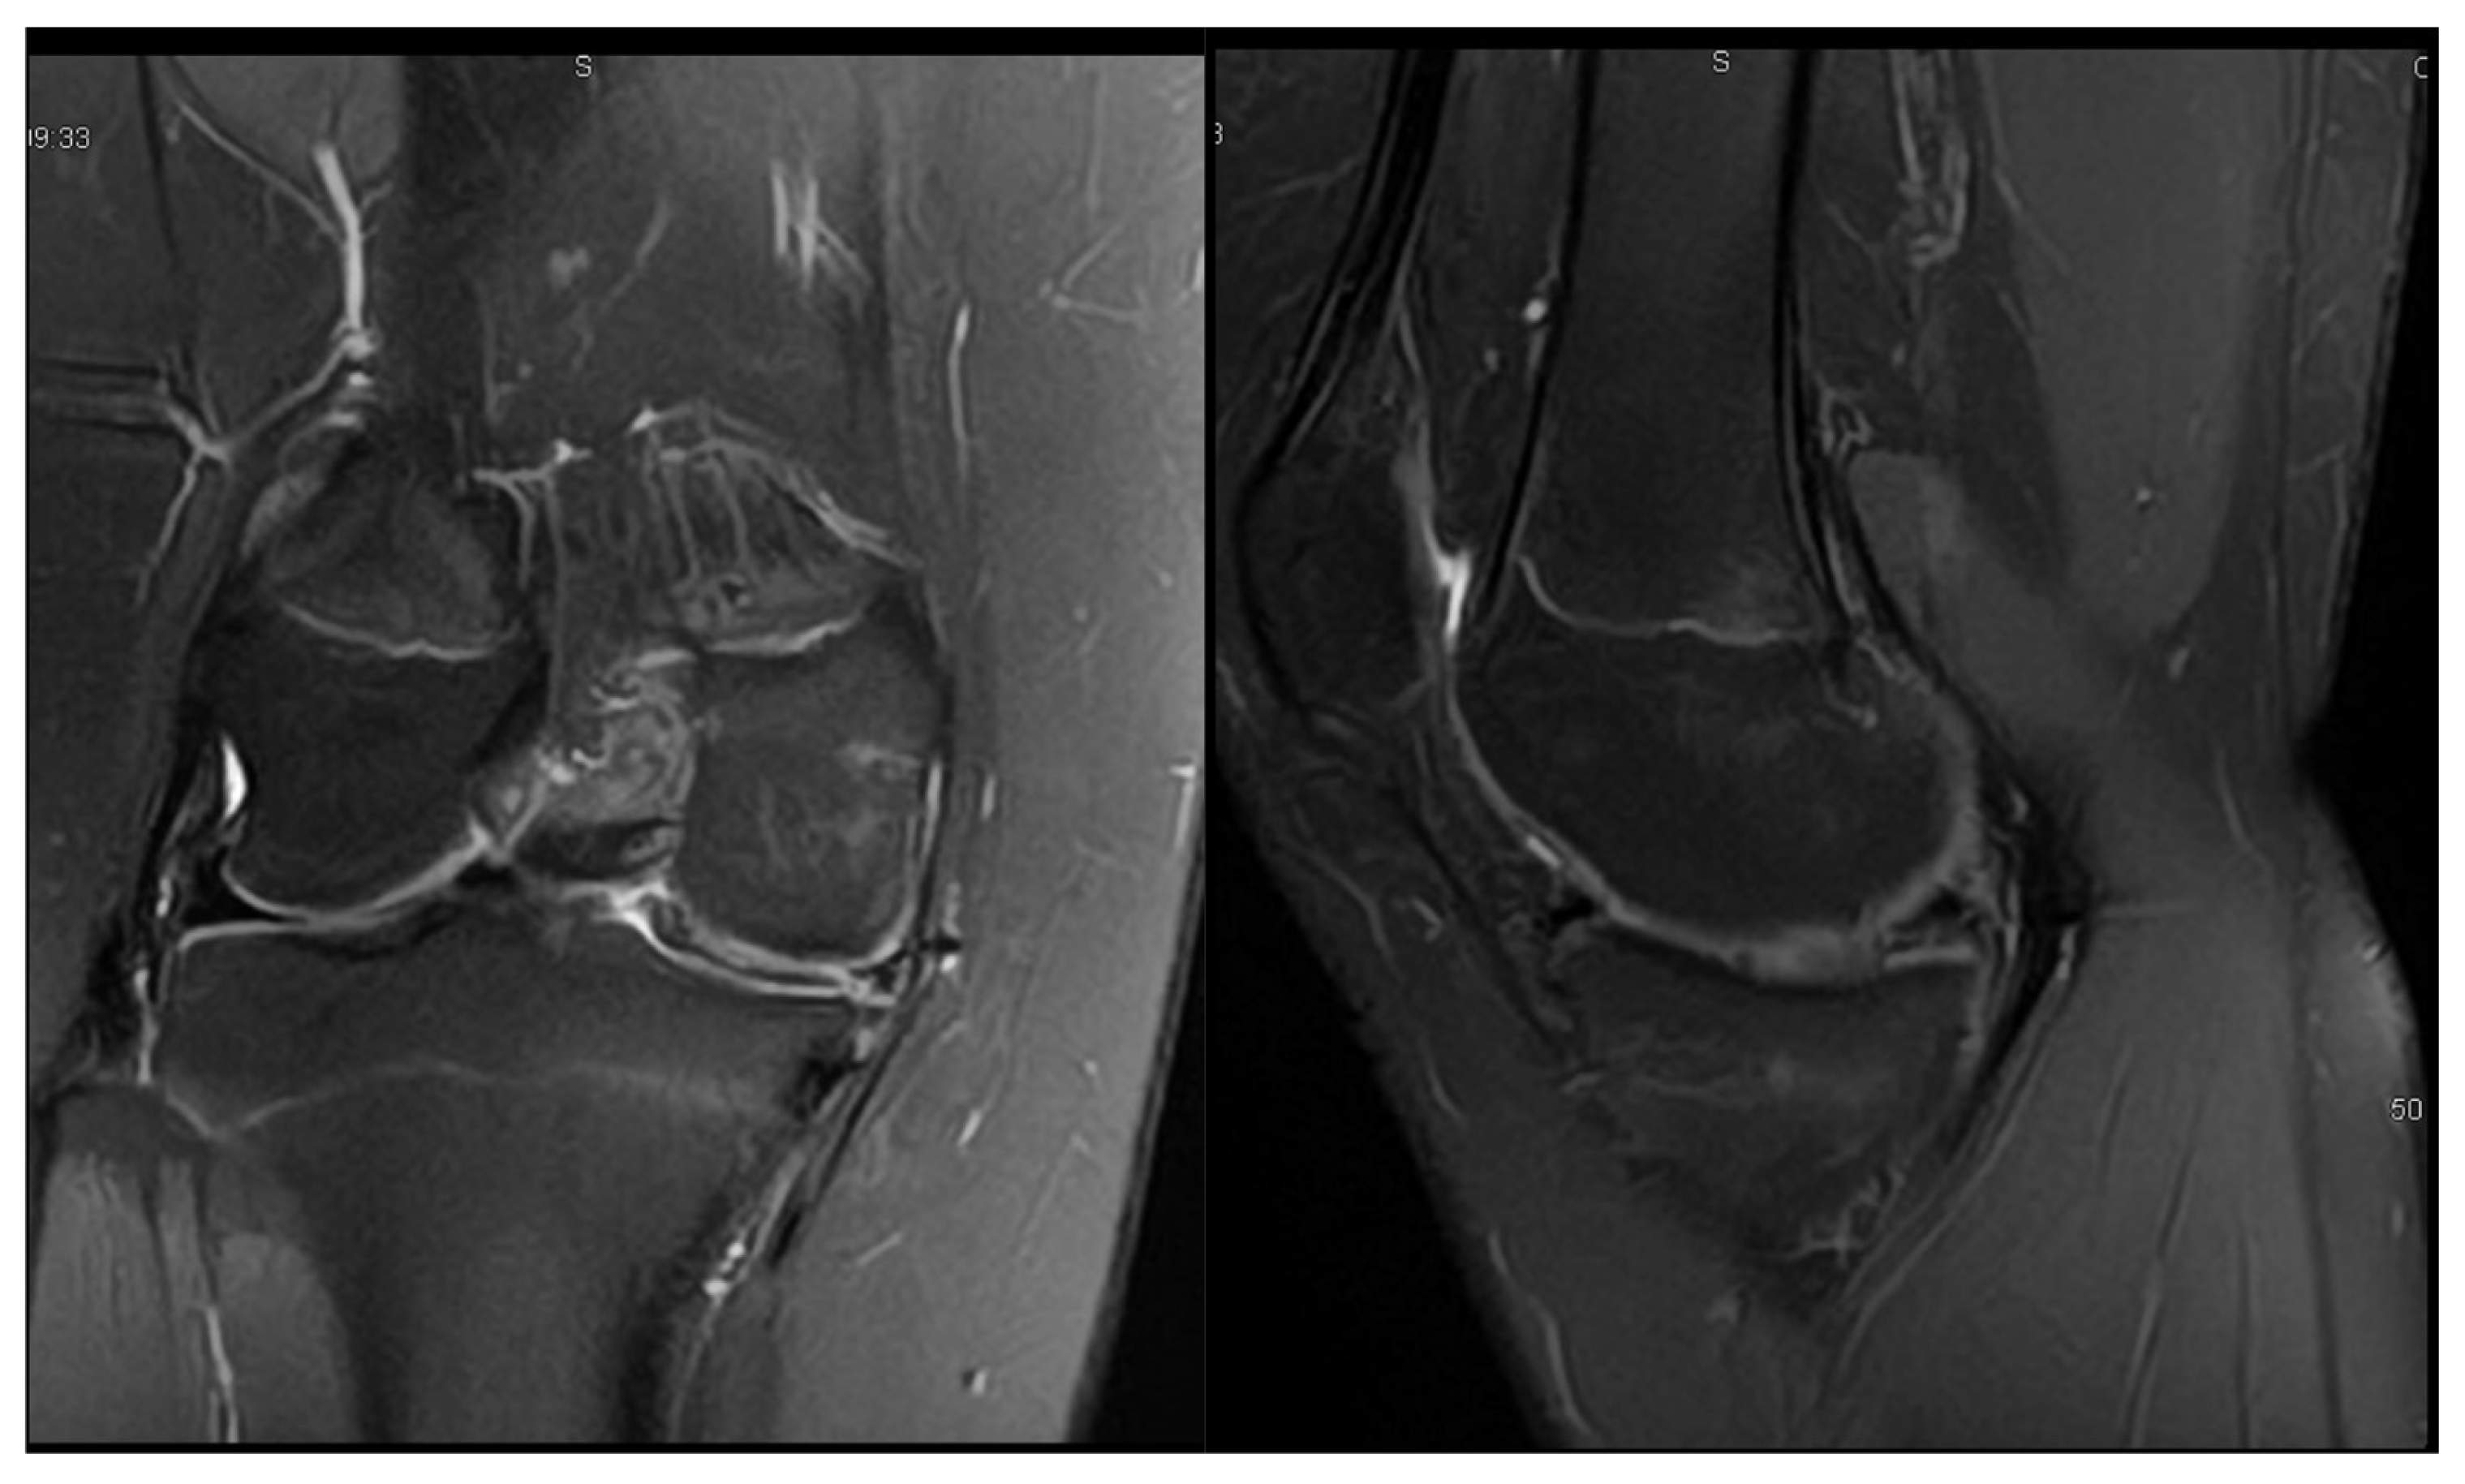

3.1. Case 1—P.E.

3.2. Case 2—S.C.S.

3.3. Case 3—G.L.

| P.E. | 12 | Bilateral (symptomatic right) | Chronic pain, effusion, normal ROM | None | 3 surgeries: partial meniscectomy (12 years), suture for horizontal tear (13 years), suture for radial tear (14 years) | 1 year after third surgery: symptom-free, resumed school sports |

| S.C.S. | 13 | Left | Pain, occasional locking, normal ROM | Dancing | 1 surgery: partial meniscectomy and suture for horizontal tear (13) | 6 months: symptom-free, full ROM, resumed dancing |

| G.L. | 14 | Bilateral (symptomatic right) | Pain, medial tenderness, normal ROM | Basketball | 1 surgery: partial meniscectomy and suture for horizontal tear (14) | 6 months: symptom-free, full ROM |